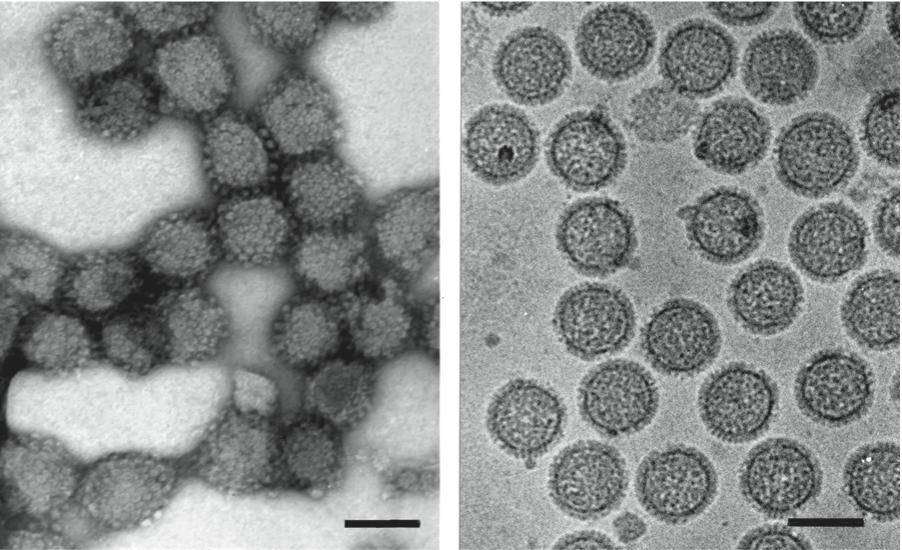

Раздел: Альбом открытий